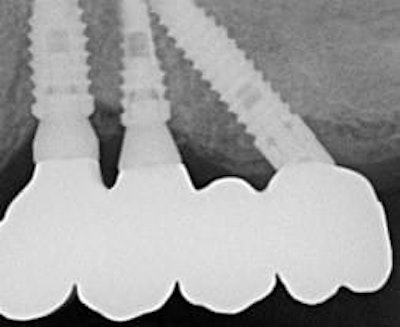

The rationale of this surgical technique is to use the tilted implant approach not only in native bone, but also in conjunction with sinus membrane distal displacement to allow a fixed prosthetic rehabilitation (Figs. 4a-d).

Occlusal and buccal vision of the final prostheses.

X-ray and CBCT post-op.

Many studies have emphasized that bone density is an important factor for implant success (6,7). The technique proposed in this article targets implant stabilization in three layers of cortical bone: the cortical layer at the osseous crest of the alveolar process, the cortical layer at the floor of the maxillary sinus, and the cortical layer of the anterior sinus wall.